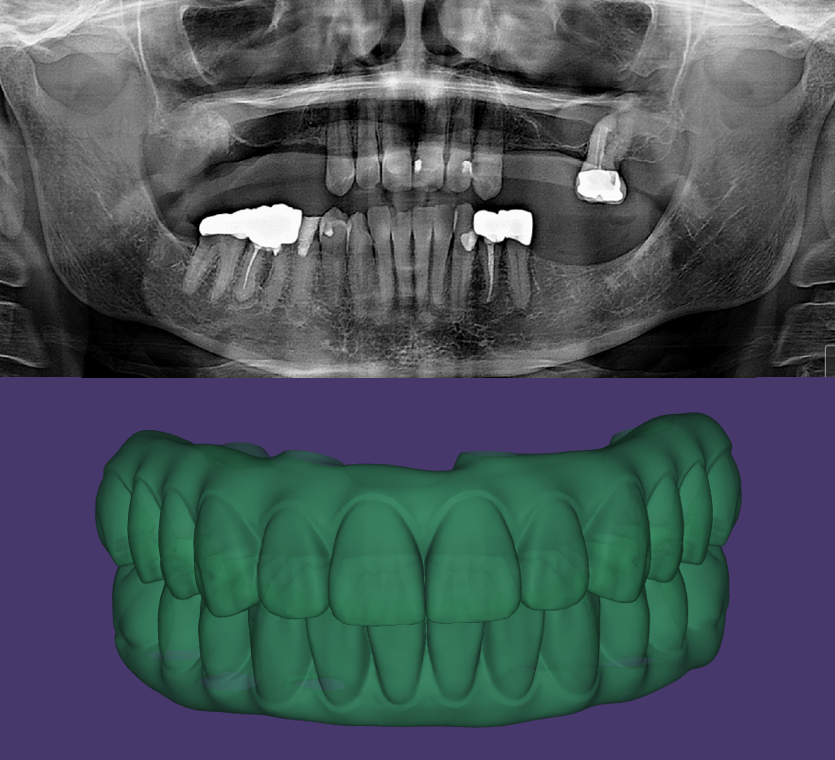

Following the PATZI protocol as always for the maxillary arch. CTV over 320Ncm. The mandibular arch is traditional All on 6 set up.

3D facially driven restorations using Instarisa facial scanner and micron mapper. Prosthesis printed using Einstein 3D printer and double arch delivered same day with little to no adjustment on occlusion.

Wonderful collaboration with Dr. Henry Sung at True Love Dental. Pterygoid implants Noris Medical @norismedical_usa @eileennorismedical Alveolar implants Neodent GM Helix @neodent_maryland_dc @paige_neodentmidatlantic @neodent.us #advancedimplantsandperiodontics #happypatient #allonx #allon4 #allonfour #dentalimplants #beforeandafter #digitaldentistry #digitaldentist #digitaldental #dentallab #dentist #dentistry #dental #smile #bestdentist #smile #lifechanging #oralsurgery #implantdentistry #surgeon #surgery #allon6 #fullarch #dream #happiness #dentalimplants #3Dfacialscanner